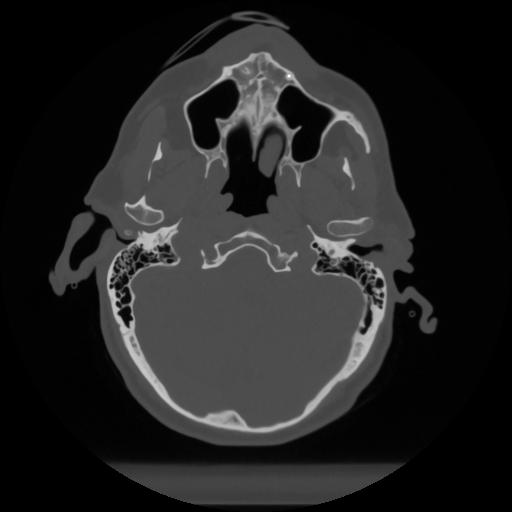

12 P.BLANDAS,,Vol,0.5,P.BLANDAS,,